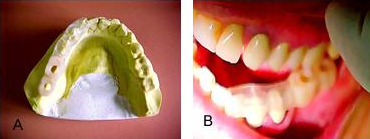

Figuras 10 A e B.

A fotografia 10 A, mostra o momento em que o guia cirúrgico foi retirado da boca do paciente onde estão fixados os monta implantes para posicionamento no modelo. Na fotografia 10B, os similares estão já parafusados e o conjunto está pronto para ser fixado no modelo que servirá para o trabalho de confecção das coroas.

Figuras 11 A e B.

Nestas fotografias o guia cirúrgico está sendo colocado em posição no modelo para fixação, antes, contudo o guia foi isolado para não ficar fixado no modelo e ser fácil de remover.